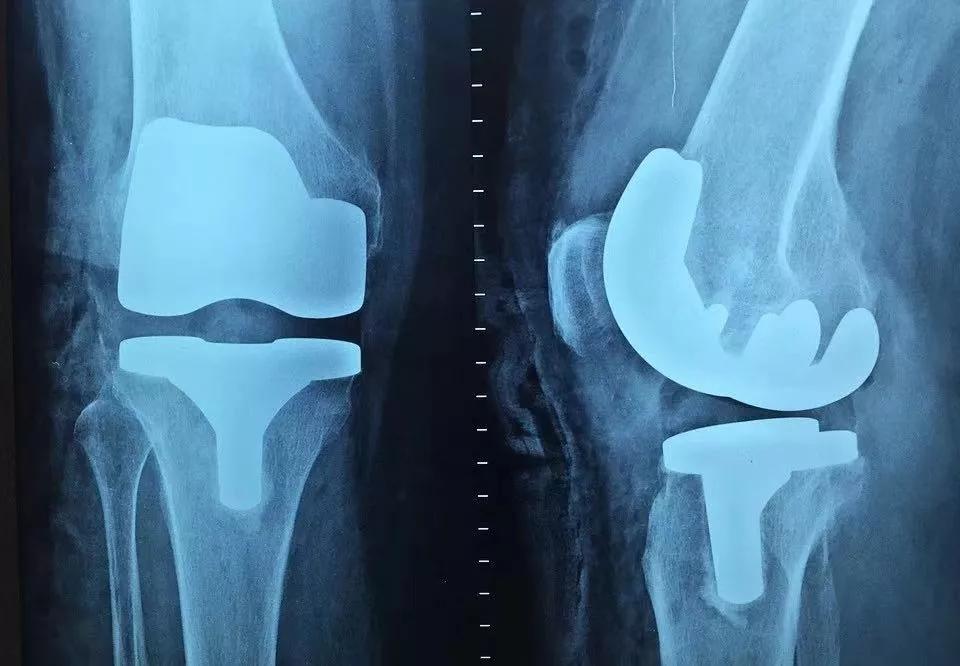

一般来说, 轻微骨刺 可以通过 适度的按摩、运动、热敷、服用镇痛药 来缓解;但 严重时 需 手术切除 ,且复发率较高;若是病情严重, 长期活动受限者 可考虑 置换关节。

膝关节的骨刺往往会合并骨性关节炎。通常会出现三种典型症状—— 疼痛、畸形、活动受限 。

具体来说,膝关节退变较轻的患者,通常在 长时间活动或上下楼、爬山等过程中出现疼痛 ,稍微休息能有效缓解;随着病情加重, 走平路时也会疼痛 ,上下楼梯或蹲起困难,甚至因膝关节内外侧骨缝磨损严重失衡而出现 畸形 。